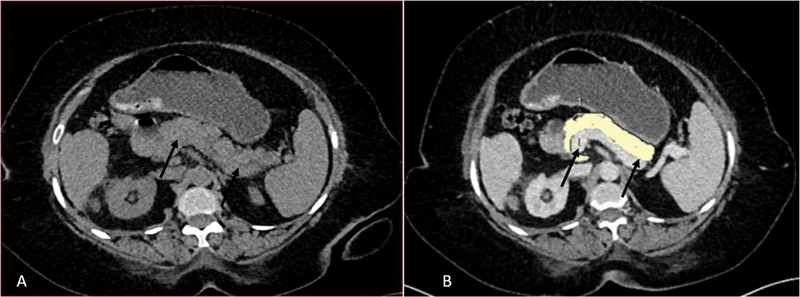

Background  The most crucial step in the management of type 2 diabetes is identifying its pathogenesis and progression. Fat accumulation in the pancreas and decreased parenchymal volume can influence pancreatic function due to insulin resistance or β-cell dysfunction. This study aims to find out the difference in pancreatic volume and fat content by using contrast-enhanced computed tomography (CECT) between normal subjects and patients with different durations of type 2 diabetes mellitus (T2DM). Methods  This was a cross-sectional study. Patients who underwent CECT abdomen for the evaluation of conditions other than pancreatic origin were included. The study group was divided into three subgroups according to the duration of diabetes as <5 years, 5 to 10 years, and >10 years. In total, 40 nondiabetic controls were included. Pancreatic fat volume and parenchymal volume were measured in cm 3 using CECT. Correlation between pancreatic parenchymal and fat volume with the duration of T2DM as well as with levels of hemoglobin A1c, random blood sugar, serum triglyceride, low-density lipoproteins, and high-density lipoproteins was done. Results  T2DM patients had significantly ( p  < 0.001) lower pancreatic parenchymal volume (mean value of 57.08 ± 8.26 cm 3 in diabetics and 72.23 ± 3.41 cm 3 in controls) and higher pancreatic fat volume (mean value of 3.08 ± 1.90 cm 3 in diabetics and 0.67 ± 0.27cm 3 in controls) as compared to nondiabetic controls. In patients with T2DM, as the duration of T2DM increased, pancreatic parenchymal volume decreased and pancreatic fat volume increased. Conclusion  Reduction in pancreatic volume and fat deposition may have a role in the onset and progression of diabetes. Determining the pancreatic volume and fat content would be useful for identifying high-risk patients and determining the pathogenesis of the development of diabetes.

Abstract Image